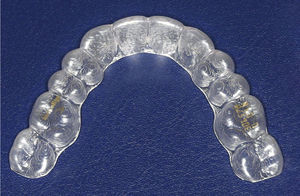

Hoy por hoy el ortodoncista tiene varias opciones de tratamiento «invisibles» a su disposición. Una de ellas es el sistema Invisalign (Align Technology, Santa Clara, EE. UU.). Fue lanzado al mercado estadounidense en 1999 y en Alemania se utiliza desde el año 2001. En estos momentos es un método de tratamiento ortodóncico con una gran difusión y con el que se ha tratado a más de 1 millón de pacientes. Con ayuda de un programa informático gráfico especial, llamado ClinCheck, se representa en 3D un objetivo terapéutico predeterminado por el ortodoncista y se fracciona en varias fases de tratamiento partiendo de la situación real de las arcadas, que se establecen en modelos de arcadas virtuales. De ese modo ClinCheck muestra paso a paso el movimiento dentario previsto en el curso del tratamiento. Para cada una de estas fases se fabrican las férulas individuales (alineadores) que el paciente debe llevar respectivamente 22h al día durante dos semanas (fig. 1). El profesional define de forma exacta el plan de tratamiento y los procedimientos llevados a cabo con ClinCheck.

La situación intraoral después de finalizar el tratamiento (figs. 16a a 16e) muestra, como lo hacen los modelos montados en relación céntrica (figs. 17a a 17e), una clase I de Angle con relación intermaxilar anterior fisiológica y una guía canina asegurada. En la radiografía panorámica final no se observan signos patológicos; se indicó la extracción de los terceros molares inferiores (fig. 18). El paciente utilizó férulas de Imprelon durante la noche como sistema de retención (Scheu-Dental, Iserlohn).